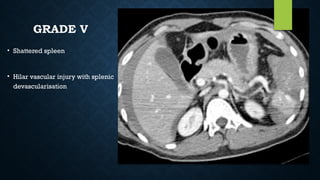

GRADE V

• Shattered spleen

• Hilar vascular injury with splenic

devascularisation

• Axial CECT scan shows

nonenhancing spleen

GRADE V • Shatteredspleen • Hilar vascular injury with splenic devascularisation

• 95.

• Axial CECTscan shows nonenhancing spleen